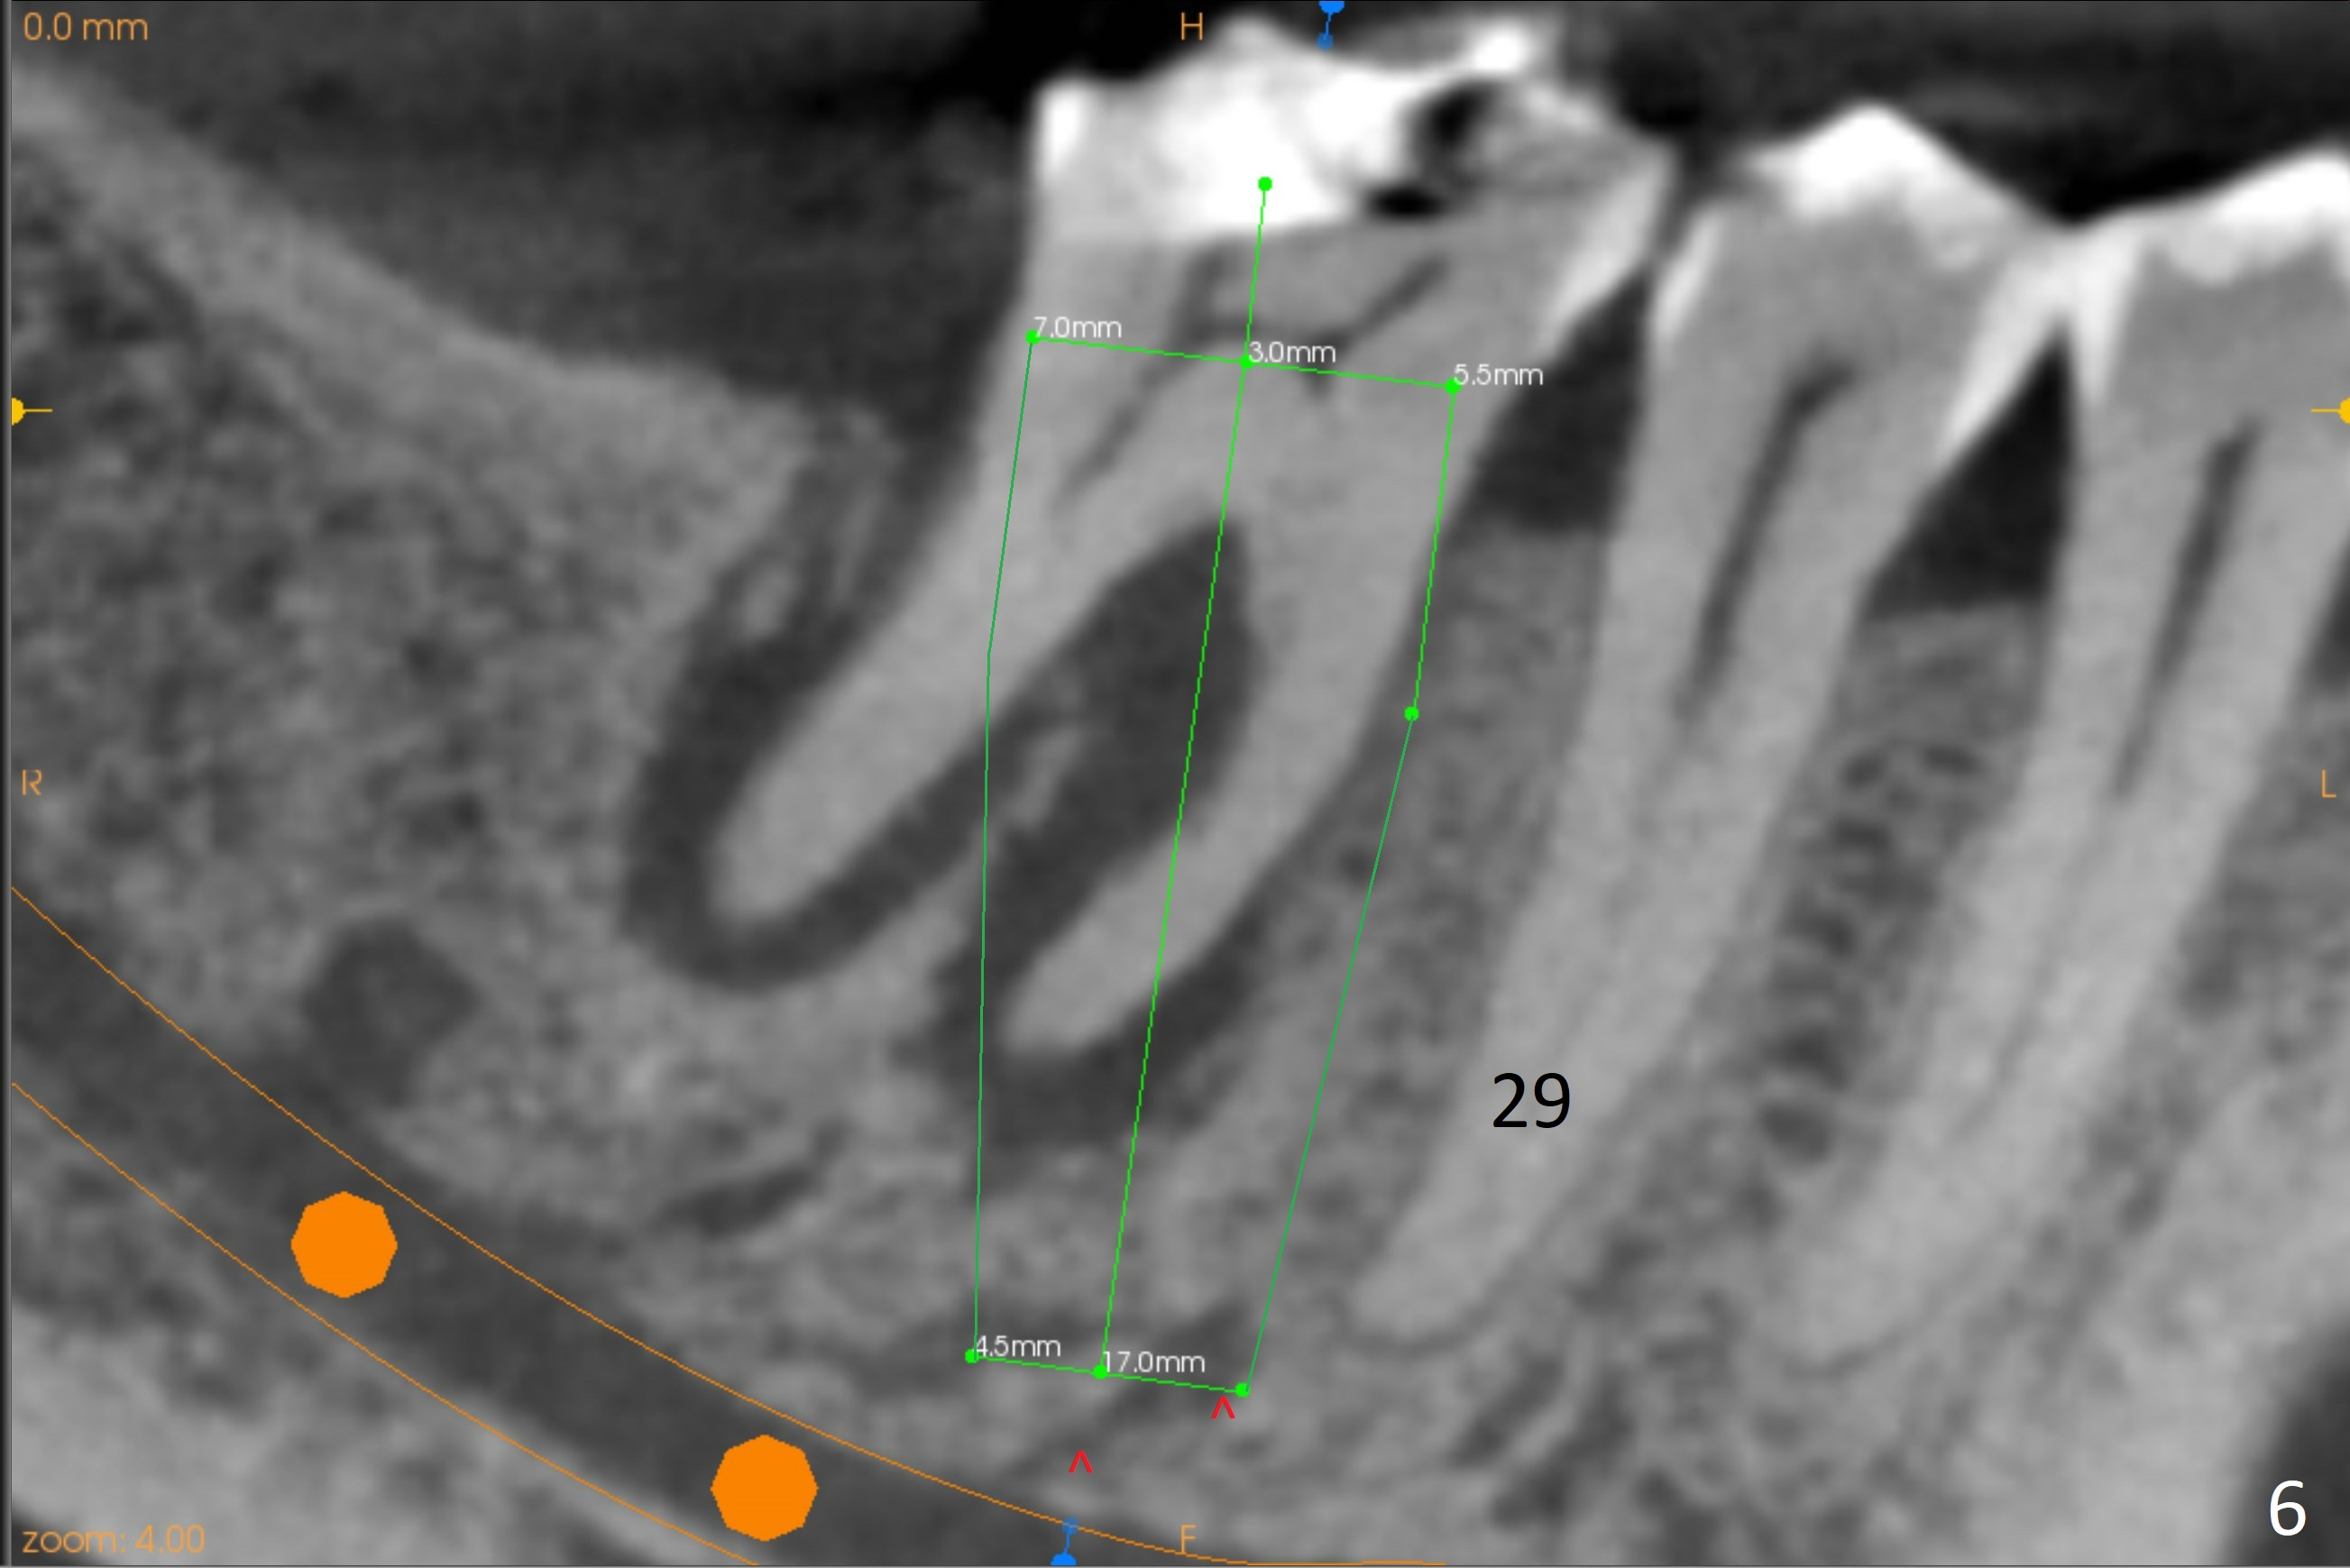

A 71-year-old woman (bruxer) wants to remove the tooth #30 (occlusal trauma, possible root fracture) for implant following the one at #14 (Fig.1). IBS abutment screw tends to loosen in functioning if the implant is placed too deep and/or off the longitudinal axis. If these two conditions are not controlled well, switch to a large tissue-level implant. A drawback of placing the implant in the septum is that the mesial margin of the abutment (Fig.2 pink) is subcrestal. If the implant is placed in the mesial socket (Fig.5 red line), the imagined abutment margin plane (white line) is parallel to the mesiodistal crests. Initial osteotomy entry point in the mesial socket and trajectory should be adjusted intraop (compare Fig.6 and 7) so that the apex of the implant will not be too close to the apex of the tooth #29 (to avoid truncating the neurovascular supply to the tooth (Fig.6 red arrowheads)) at the same time the abutment inclination is not too compromised (Fig.7). To prevent pressure upon the buccal (Fig.4 B) plate, osteotomy should be slightly lingual and/or the diameter of the implant is to be < 7 mm. Use a 3 mm unipost for provisional and probably 5 mm one for definitive restoration. Apply bonding to the post if the implant is 6 mm or less. The provisional margin should be wide and deep for deep margin and easy impression later. Use IS drills with 4 mm stopper for osteotomy if the septum is absent. Prepare Rongeur and surgical handpiece to remove the remaining septum if needed. Be wary of the distally curved root tip of #29. In fact there is a mesiodistal crack line (Fig.8 arrowheads) with buccal recession (Fig.9, 2 weeks preop).